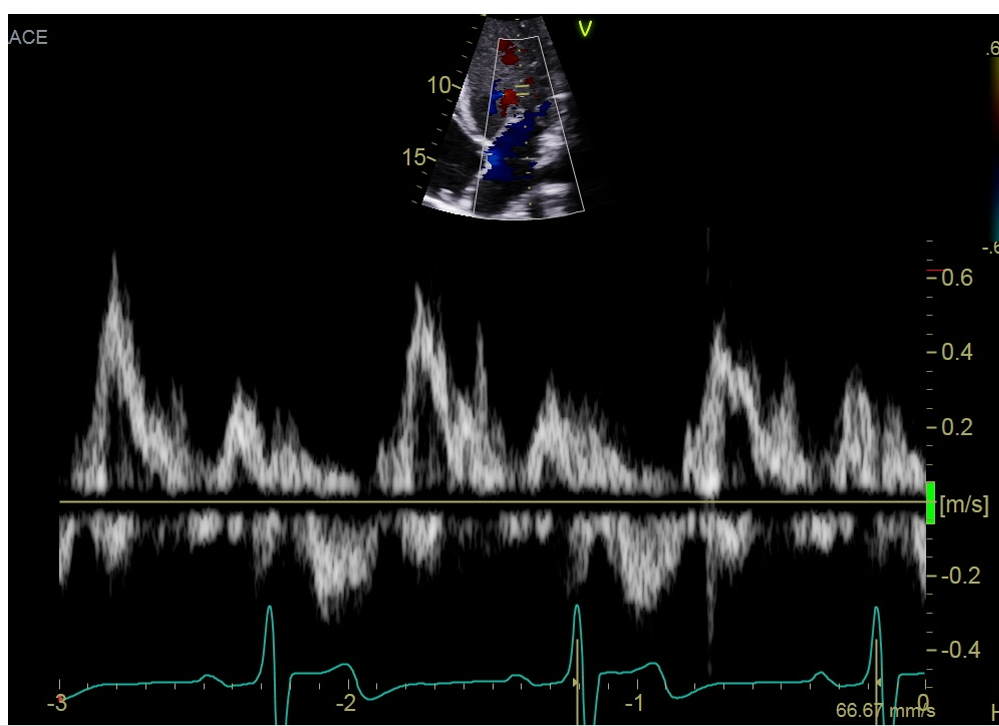

what single is this measurement for what are you going to peak, why would this doppler be important

this measure is for the pulmonary vein

Pulmonary vein peak systolic velocity (peak the S wave)

Peak D wave

peak the velocity of the atrial reversal or atrial duration

This will important when interrogate for MR, If the S wave is shorter than ourt D that is blunting so this coulf point to moderate or severe regurgitation if you see a reversal in these two